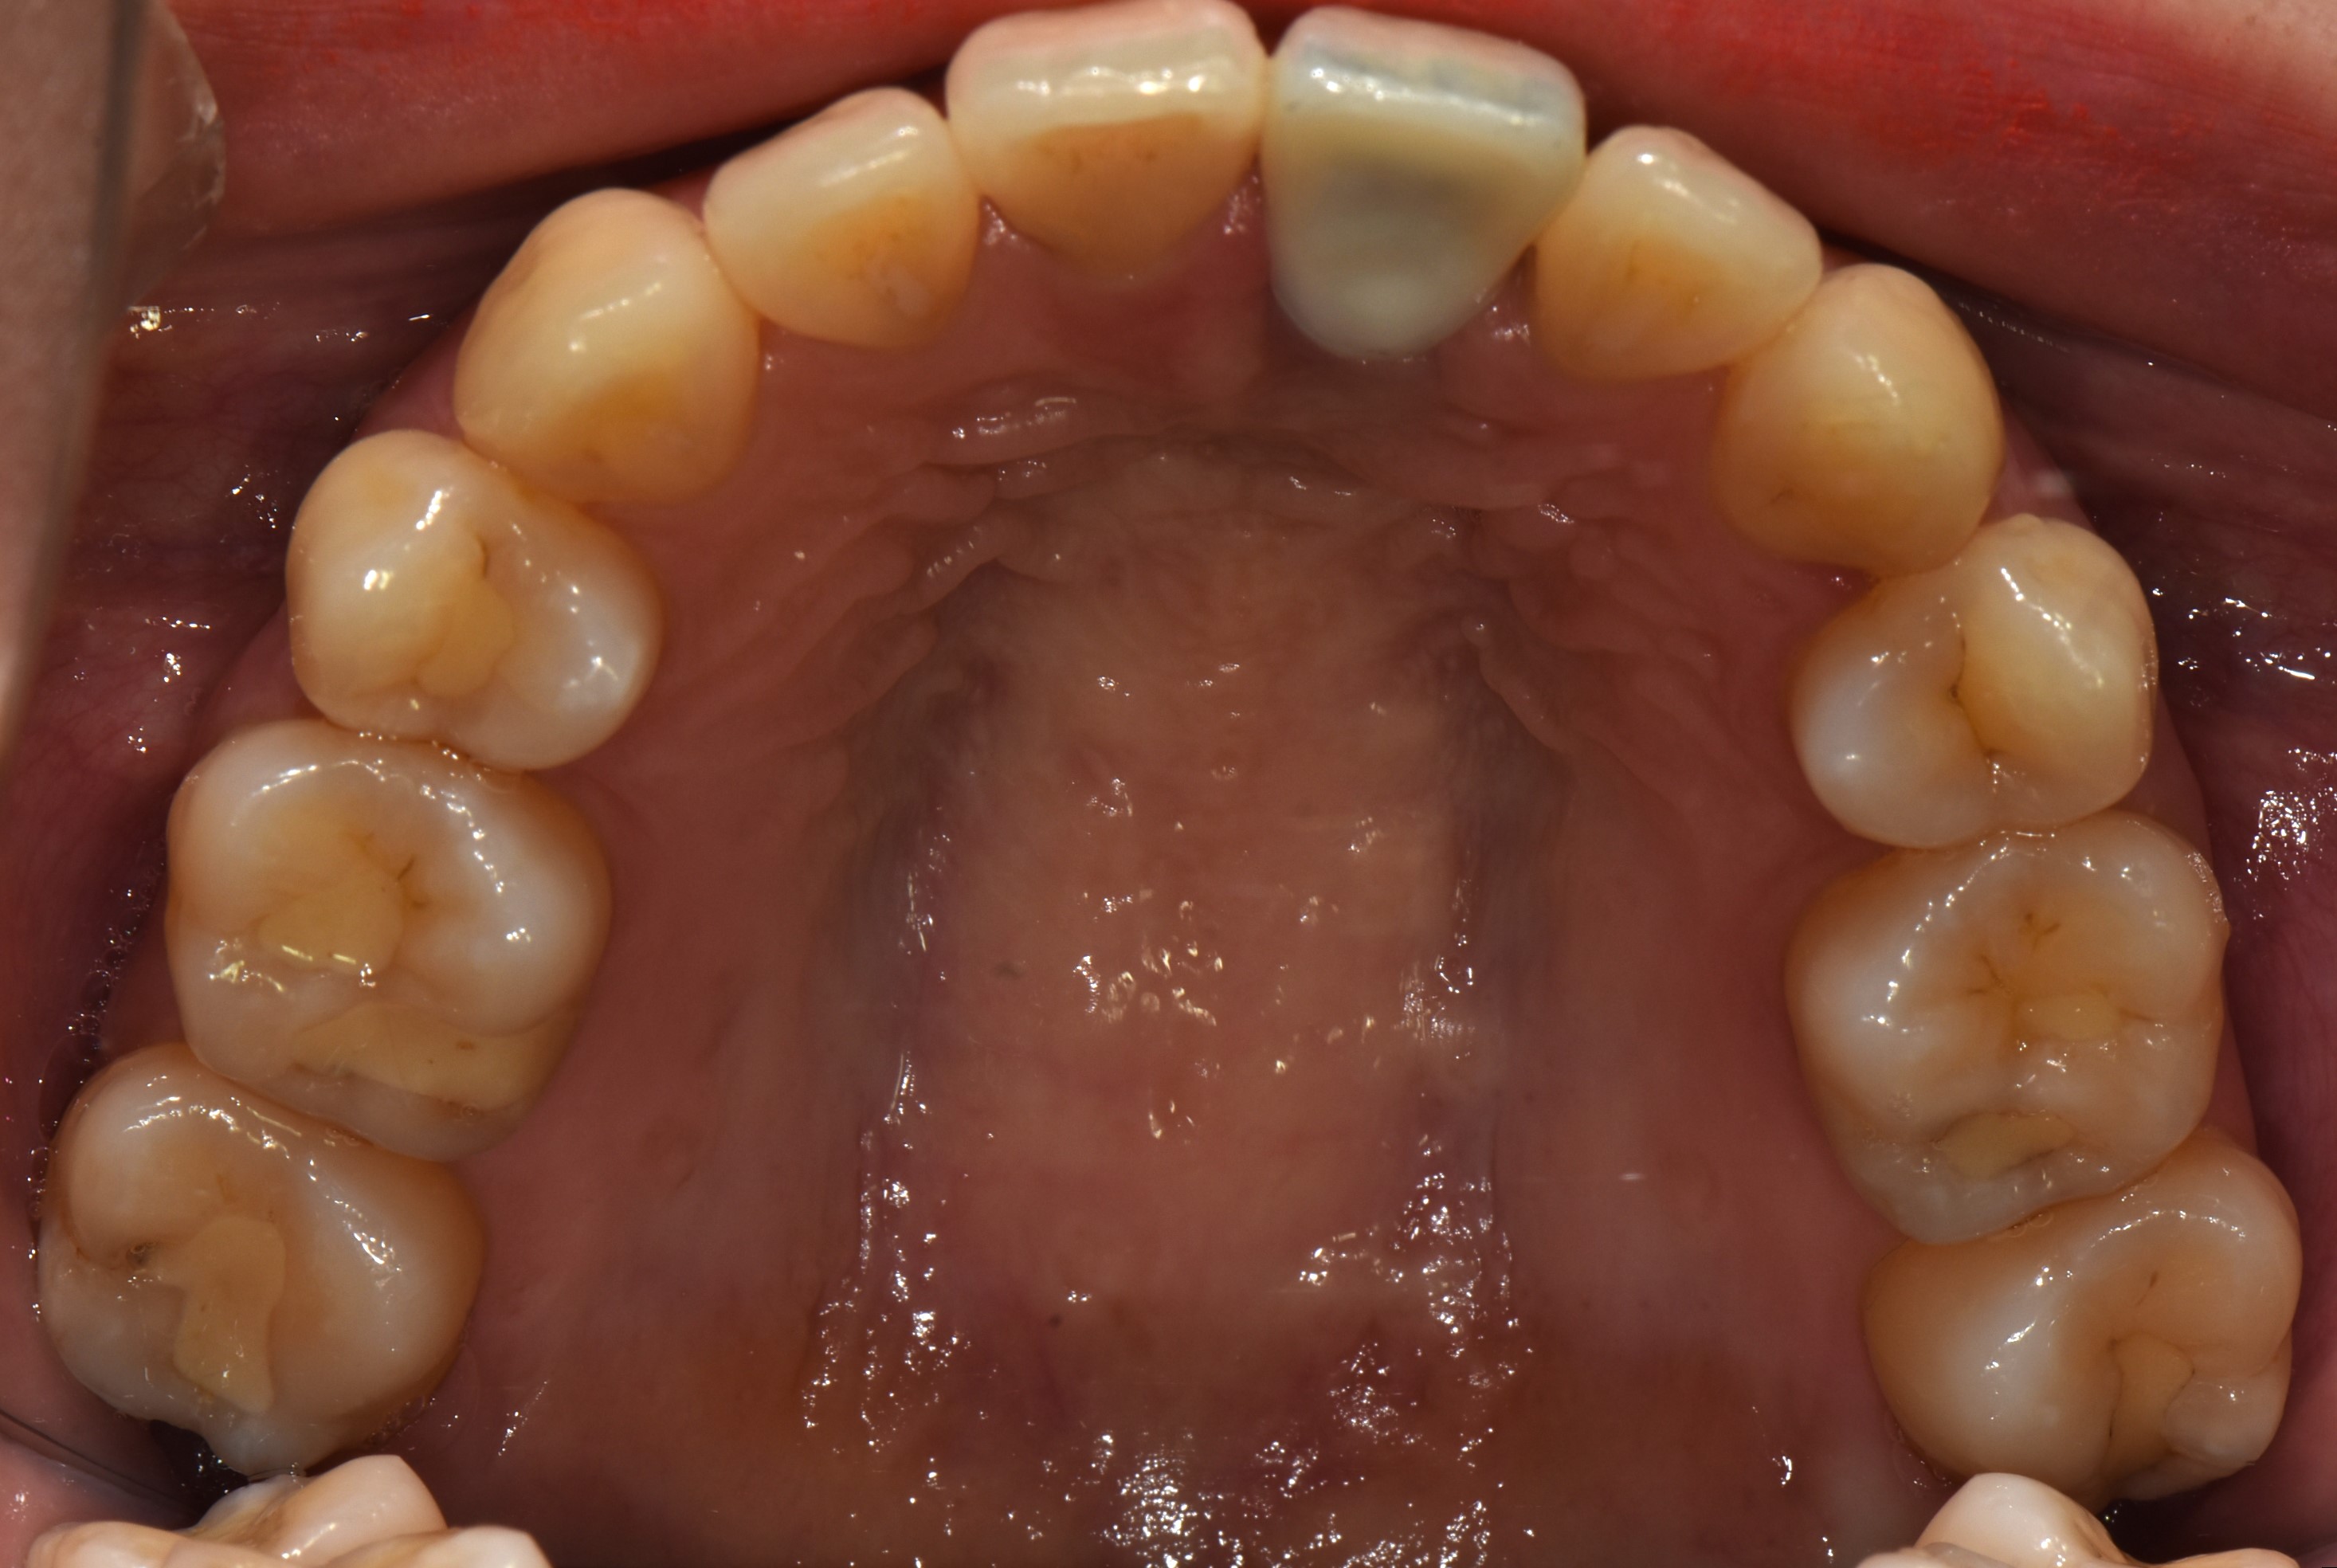

치료 후 사진입니다.